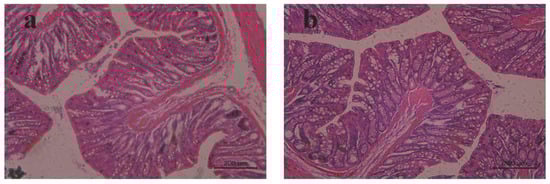

2.9. Rat rectal Mucosal Irritation

The safety test was performed to observe any irritation or damage to rectal tissues in rats after the rectal administration of MLX/HP-β-CD-ISG. There was no abnormality in the rectal tissue observed by the naked eye. After histopathological sections were stained, the local mucosal epithelium of the rectum in the blank control group and the MLX/HP-β-CD-ISG group was intact, and there was no obvious inflammatory cell infiltration, edema or ulcer (Figure 10). This showed that MLX/HP-β-CD-ISG had no irritation or damage to the rectum.

Figure 10.

The pathological changes in the rectal tissue of rats in each group after rectal administration (HE × 200): (a) blank control group and (b) MLX/HP-β-CD-ISG rectal administration for 24 h.